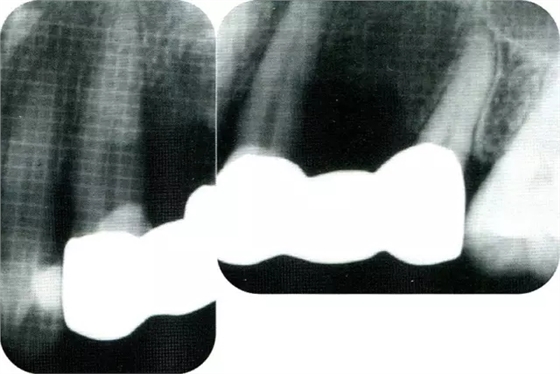

▲圖8-2初診時(shí)的x片。尖牙遠(yuǎn)中確認(rèn)有垂直性骨缺損。

▲圖8-3進(jìn)行全厚瓣翻瓣,將根表面的沉積物、骨缺損的肉芽組織徹底清除,確認(rèn)牙槽骨形態(tài),可看到從頰側(cè)到遠(yuǎn)中存在垂直性和水平性的骨缺損。